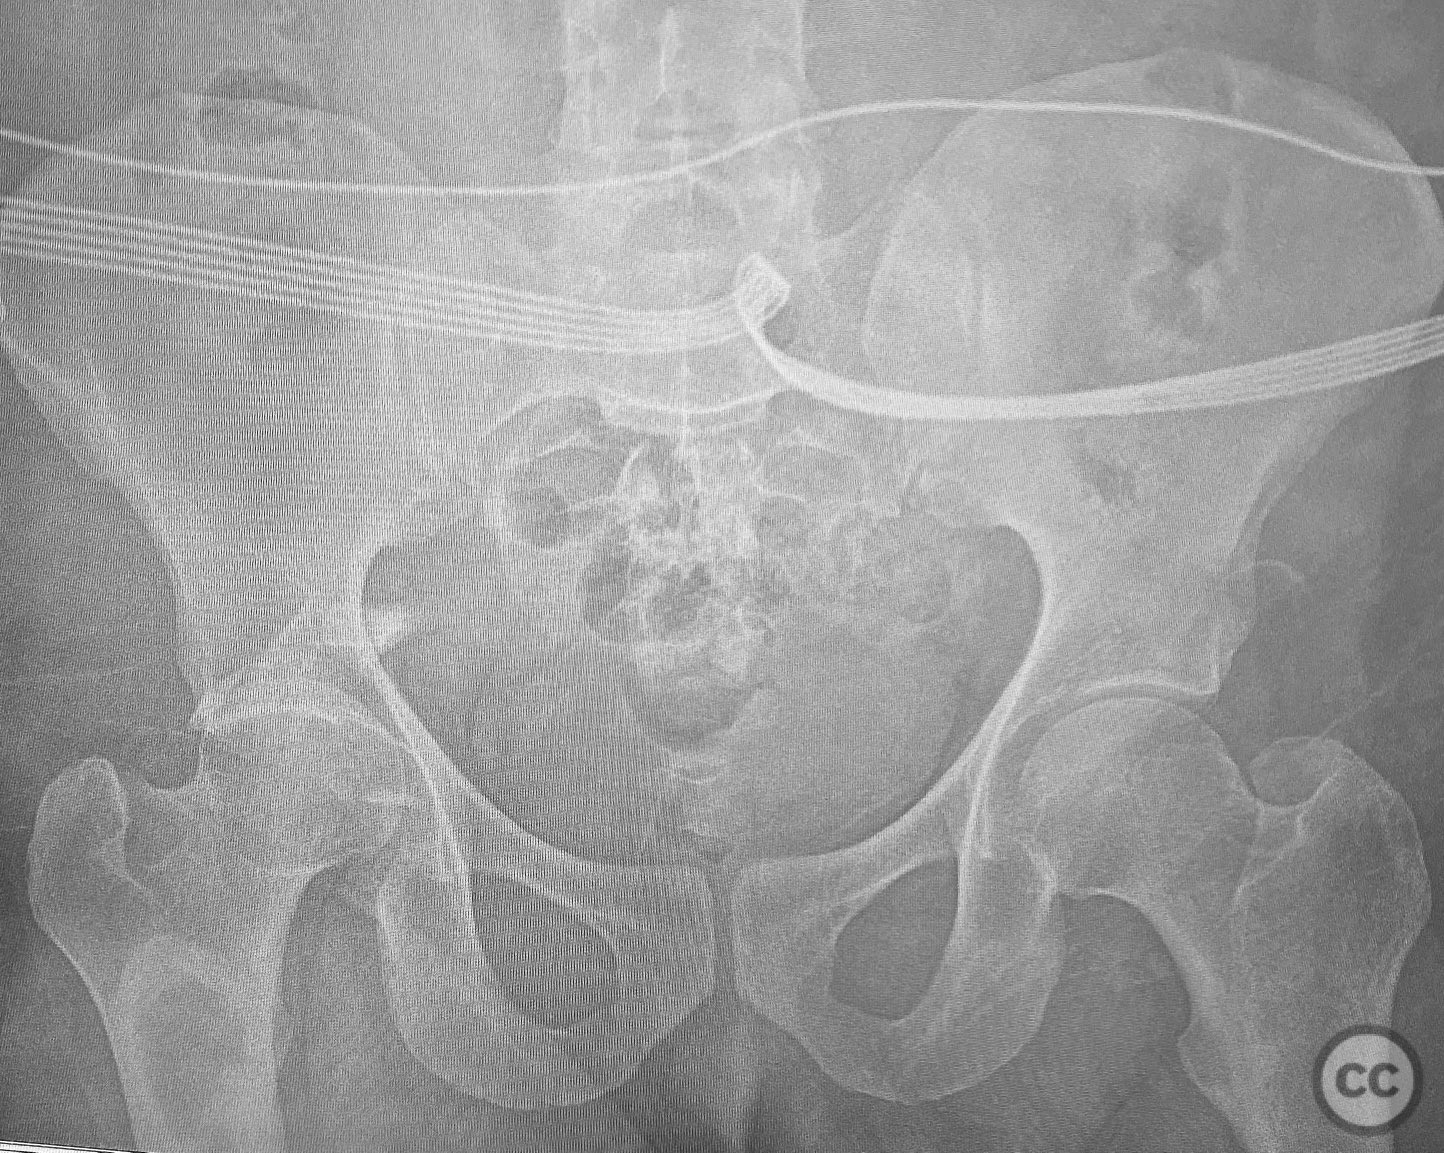

Clinical and radiological findings:  A patient sustained a comminuted posterior wall acetabular fracture-dislocation (AO/OTA 62-B1.3) involving the greater sciatic notch, with associated traumatic sciatic nerve injury. Following closed reduction, imaging demonstrated an intra-articular fragment located within the acetabular fossa (fossa acetabuli). Clinical examination revealed neurological deficit consistent with sciatic nerve involvement. Radiographs and CT confirmed the extent of comminution and intra-articular displacement.

Planning remarks:  The preoperative plan included a Kocher-Langenbeck (KL) approach in the prone position for open reduction and internal fixation of the posterior wall fragments, removal and reduction of the intra-articular fossa fragment, and exploration of the sciatic nerve with neuroplasty. Fixation was planned using a combination of standard plates and a spring hook plate to address the cranial wall fragment.